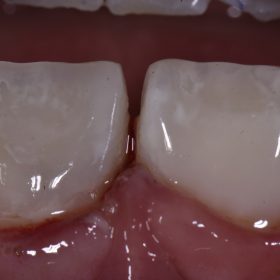

Large Tooth Fracture Repair | ACC | Cosmetic Bonding Auckland

Happy Friyay, Huge Class IV fracture secondary to fracture on a 10 year old girl. Clear violation of biologic width, but parents wish to “see how she heals” before deciding […]